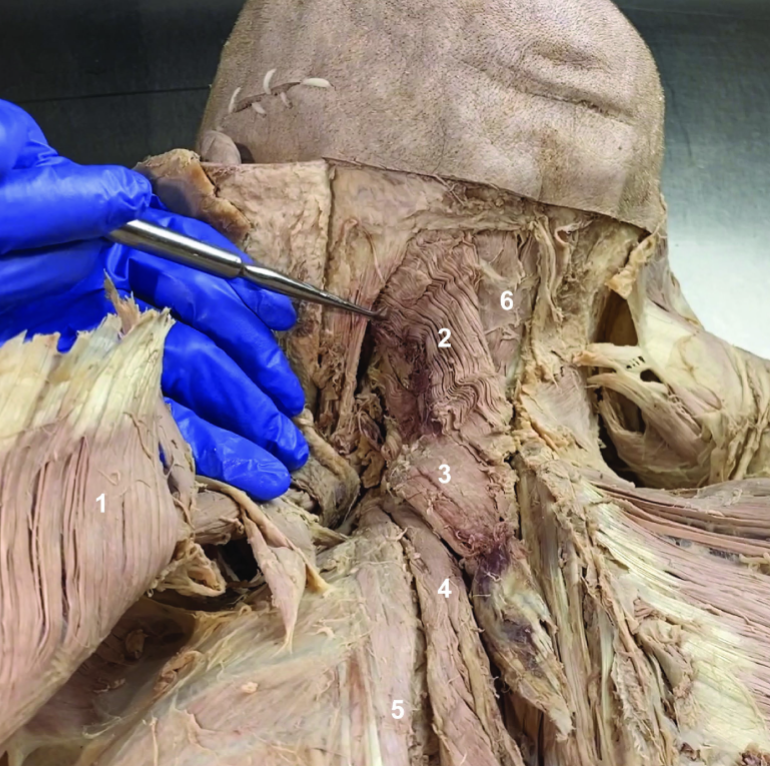

Trapezius (reflected)

ID structure

Spinal accessory n. (CN XI)

ID structure

Transverse cervical a.

ID structure

Levator scapulae

ID structure

Rhomboid minor

ID structure

Rhomboid major

ID structure

Rhomboids (reflected)

ID structure

Splenius capitis

ID structure

Splenius cervicis

ID structure

Longissimus

ID structure

Iliocostalis

ID structure

Semispinalis capitis